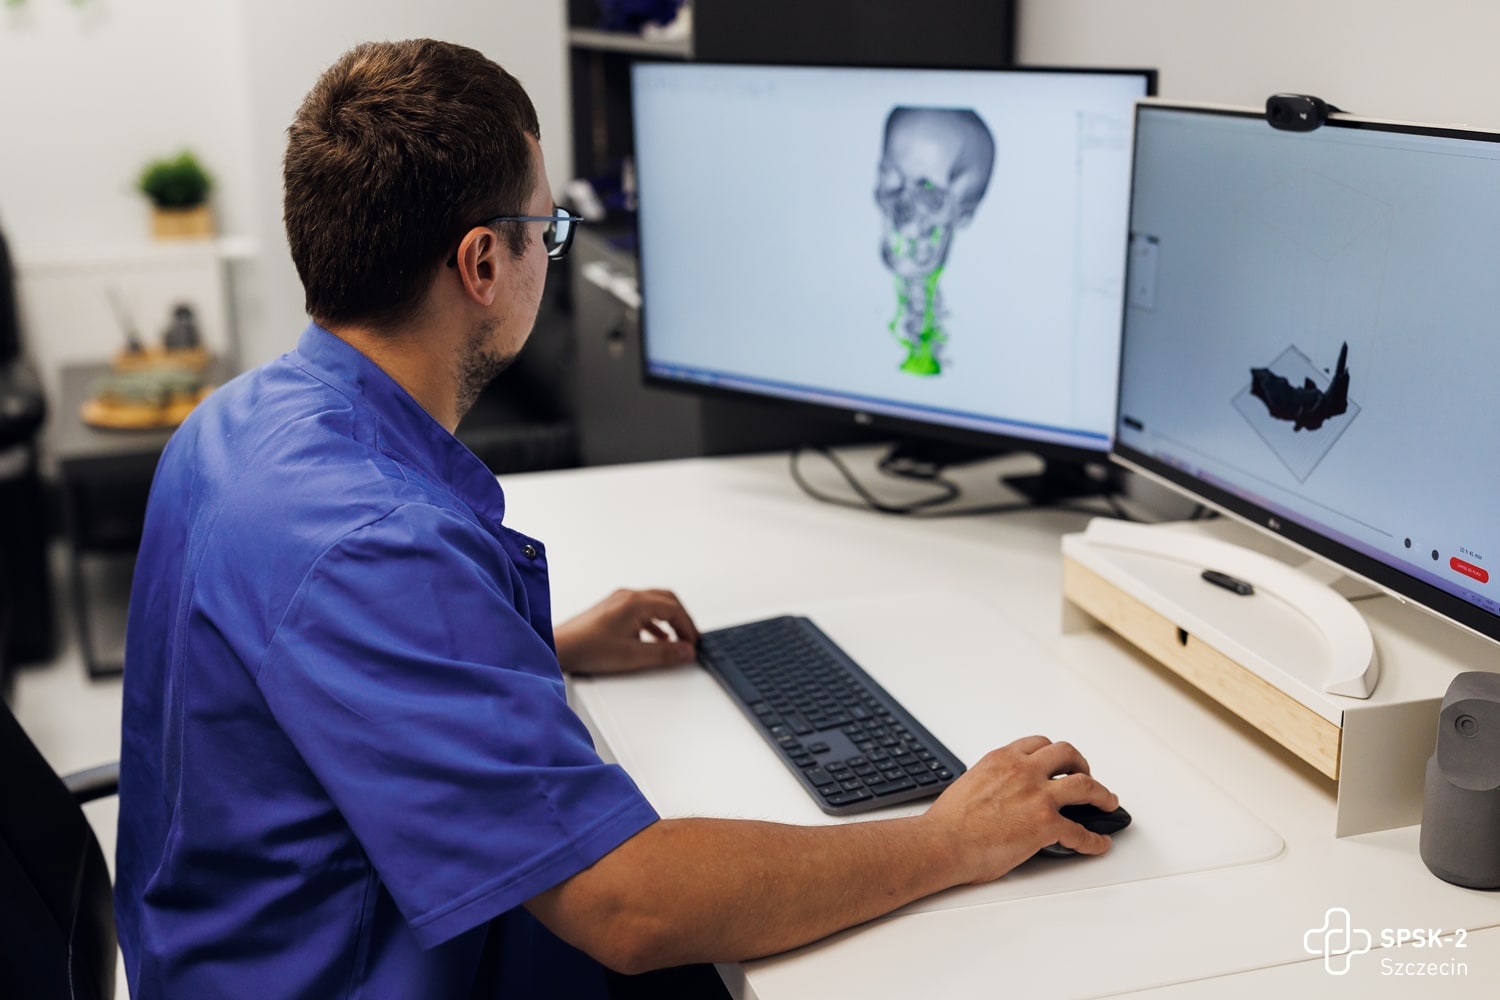

Oprócz badań USG chętni mogli zaznajomić się z najnowszymi metodami leczenia tętniaków aorty, obejrzeć filmy, w których nasi chirurdzy naczyniowi opowiadają o zagrożeniach chorobami naczyniowymi, zobaczyć na własne oczy czym jest tętniak i jak wygląda, obejrzeć wydrukowane w Ośrodku Technologii Medycznych 3D naszego szpitala modele organów człowieka, oraz poczuć się jak chirurg podczas operacji i dzięki goglom Hololens i wyświetlanemu w nich obrazowi rozszerzonej rzeczywistości ponawigować obrazem tomografii komputerowej i dokładnie obejrzeć struktury anatomiczne człowieka.

Pielęgniarki i położne naszego szpitala: Aleksandra Dreas, Alicja Kapała, Klaudia Kokoszka, Ewa Kubiak oraz stażyści i studenci Pomorskiego Uniwersytetu Medycznego w Szczecinie: Katarzyna Czarnecka, Karolina Kalembkiewicz, Michał Kargul, Dominika Kucharska, Karolina Seidler, Urszula Sielicka, Patryk Skórka, Claudia Wietrzykowska mierzyli ciśnienie, poziom glukozy we krwi i przeprowadzali wstępną kwalifikację pacjentów do badań oraz pokazywali jak rozszerzona rzeczywistość pomaga zobaczyć to, czego nie widać gołym okiem. Dr n. med. Paweł Rynio, chirurg naczyniowy i kierownik projektu – chętnie opowiadał o chorobach naczyniowych i tłumaczył m.in. jak technologia druku 3D wspiera medycynę.

Jedyny w kraju Ośrodek Medycznych Technologii 3D otwarty!

2022-10-13Po kilku latach wyczekiwania 7 października 2022 roku odbyła się uroczystość formalnego rozpoczęcia działalności nowoczesnego Ośrodka Medycznych Technologii 3D. To jedyna taka w Polsce, pierwsza, niepowtarzalna jednostka, która łączy zaawansowane technologie druku 3D, gogle mieszanej rzeczywistości i medycynę! Korzystać z tego będą mogły wszystkie dziedziny medycyny, nie tylko szczecińskich, czy polskich szpitali.

Celem Ośrodka Medycznych Technologii 3D jest:

- optymalizowanie sposobów leczenia

- indywidualizowanie opieki nad pacjentem, poprzez tworzenie trójwymiarowych modeli organów pacjenta

- rozwijanie i polepszanie metod operacyjnych.

Dostępne na co dzień dwuwymiarowe wyniki badań chorego – tomografia komputerowa, czy rezonans magnetyczny, to lata temu był skok w przyszłość. Dziś to już trochę za mało. Trzeci wymiar obrazu struktur anatomicznych chorego to ten element, który niezwykle ułatwia pracę lekarzowi. By stworzyć trójwymiarowy obraz z pomocą przychodzi druk 3D oraz hologramy.

W Ośrodku Medycznych Technologii 3D (OMT3D) powstać będą trójwymiarowe modele organów pacjentów – prawidłowe lub ze zmianami patologicznymi. Wydruk będzie powstawał w najnowszej generacji drukarkach 3D, umożliwiających druk nie tylko dowolnych struktur anatomicznych pacjenta z ich patologiami, ale odwzorowujących także kolory, strukturę, giętkość i twardość prawdziwych organów i tkanek. A dzięki goglom Hololens2, operujący lekarz będzie w powietrzu nawigował hologramem, przedstawiającym zdjęcia diagnostyki obrazowej pacjenta.

Pomysłodawcą powstania ośrodka jest dr n. med. Paweł Rynio – młody lekarz, chirurg naczyniowy, który rozwinął ideę w ramach programu Interreg VA, w którym partnerem naszego szpitala jest Uniwersytet Medyczny w Greifswaldzie. Jak mówił podczas uroczystości otwarcia Ośrodka przedstawiciel partnera - prof. Maciej Patrzyk – „Trzeci wymiar obrazu diagnostycznego pacjenta to było coś, czego brakowało lekarzom w medycynie. Płaskie obrazy nie oddają rzeczywistości na tyle dokładnie. Kiedy zobaczyłem w telewizji, że zespół prof. Gutowskiego w szpitalu w Szczecinie wykorzystuje druk 3D i gogle mieszanej rzeczywistości, wiedziałem, że tego szukam. Kiedy więc dr Rynio zadzwonił do mnie, to razu przystałem na współpracę”